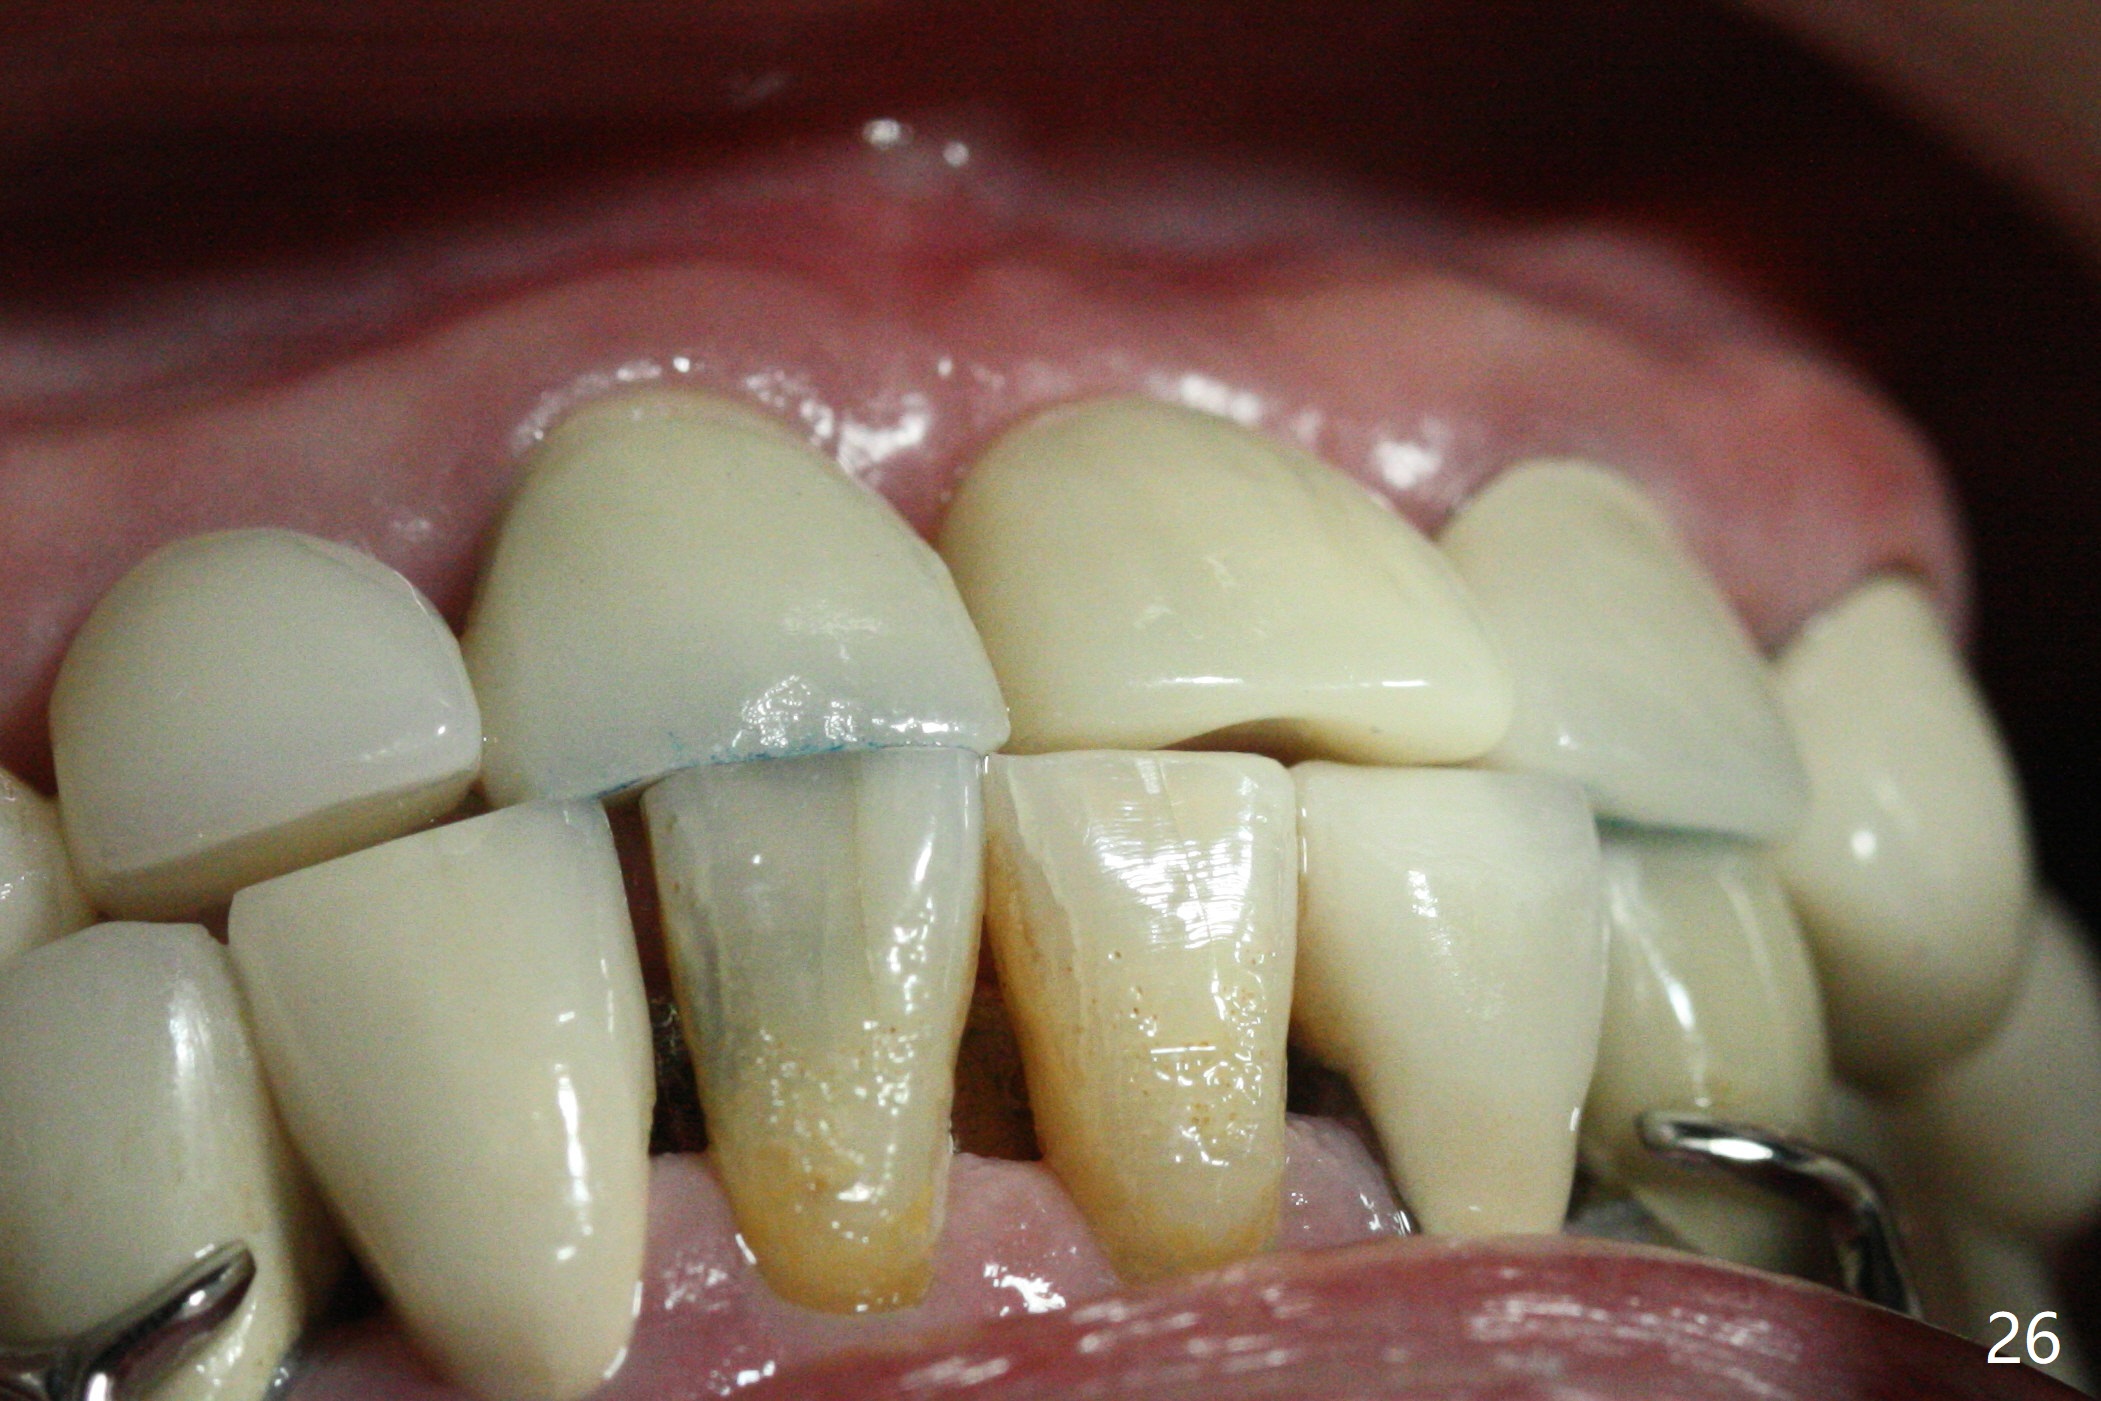

The buccal contour at #9 seems to be slightly concave preop (Fig.1,2 (*)). In fact the buccal plate is found to be lost when the tooth is extracted. Osteotomy is initiated as palatal as possible apical, but the occlusion dictates the coronal end of the osteotomy should be buccal, leaving the buccal gap ~ 2 mm for bone graft. The initial osteotomy (18 mm deep) appears to be close to the Incisive Foramen (Fig.3 blue dashed line). The nasal floor appears to be intact when the drill is removed. Subsequent osteotomy is adjusted so that the apical end of the osteotomy moves distal; when a 3.8x15 mm dummy implant is partially placed, there is clearance (Fig.4). It remains so when a definitive implant is seated (Fig.5); Vanilla graft is placed (Fig.5 *) before placement of a 4.5x5.5(3) mm abutment. More allograft is placed when an immediate provisional is fabricated (Fig.6 arrow and *). The gingiva remains to be recessive 1 month postop (Fig.7). It seems to be related to the bulky gingival margin of the provisional (Fig.8 *). After trimming the latter (Fig.9 *), the gingival margin immediately returns close to normal (Fig.10). The gingival margin is even between #8 and 9 two months postop, but the bone graft is exposed apically (Fig.11 ^). It may heals by itself. Otherwise debridement, regraft, PRF and suture are pending. The coronal portion of the socket heals 4 months postop (Fig.12). The gingival cuff forms by the immediate provisional (which is removed for impression) 4 months postop (Fig.13 *). While the full Zirconia crown at #7 remains intact (Fig.14), the PFM at #9 has porcelain chip (Fig.15). It is partially due to the occlusion; while the crown at #7 has clearance with the opposing dentition (Fig.16 *), the one at #9 has no. The access hole at #9 (Fig.17 *) seems to weaken the crown structure. There is no access hole at #7. No solid posterior support is another contributing factor for chip (Fig.18). The buccal plate has mild atrophy at #7 and 9 (Fig.19 *). A piece of bone graft is being expelled apically at #9 (Fig.20 >) and is removed subsequently (Fig.21). Before impression for repacking porcelain, the opposing incisal edge has been shortened (Fig.22 arrows, as compared to Fig.16). Since the ideal access hole is at the incisal edge (Fig.25 black circle), buccal to the existing one (Fig.24 A), the abutment is torqued before the repaired crown is recemented (Fig.23). Finally the crown has occlusal clearance (Fig.26). Porcelain chips again around the access hole of PFM 1.5 years post 2nd cementation. The dense bone at the crest (*) cannot explain why the abutment is not loose, since it remains incompletely seated (>). As it was trimmed short, an angled abutment is used (Fig.28). The coronal end is lingual, while #9/24 is edge to edge. The lingual aspect of the coronal end of the abutment is heavily trimmed to reduce bulkiness. To prevent chip, Zirconium crown will be fabricated in spite of the fact that it does not match the PFM of #8 (potential shade discrepancy). The patient is pleased with the new Zirconia crown (Fig.29).